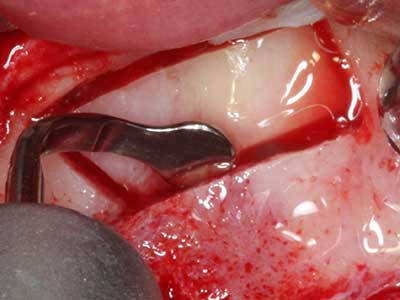

Както е отбелязано по-горе, индикациите за пиезохирургия могат да бъдат открити и в сферата на консервативната дентална хирургия. Специалните работни накрайници улесняват разкритието на кореновите канали и предпазват нервите и мукозната мембрана на синуса, особено в долния премолар и горната дистална зона на зъбите. Извитите диамантени накрайници се използват за прецизна подготовка за резекция на кавитета за ретроградно запълване на канали на незакрита апикална обтурация. Ултразвуковата технология позволява накрайниците да бъдат много тънки, като това подобрява видимостта и размера на достъпа до кавитета. В резултат, приложението на ултразвукова хирургия за тази индикация е една от стандартните процедури за апикална резекция (Del Fabbro, Tsesis et al. 2010, Scarano, Artese et al. 2012).